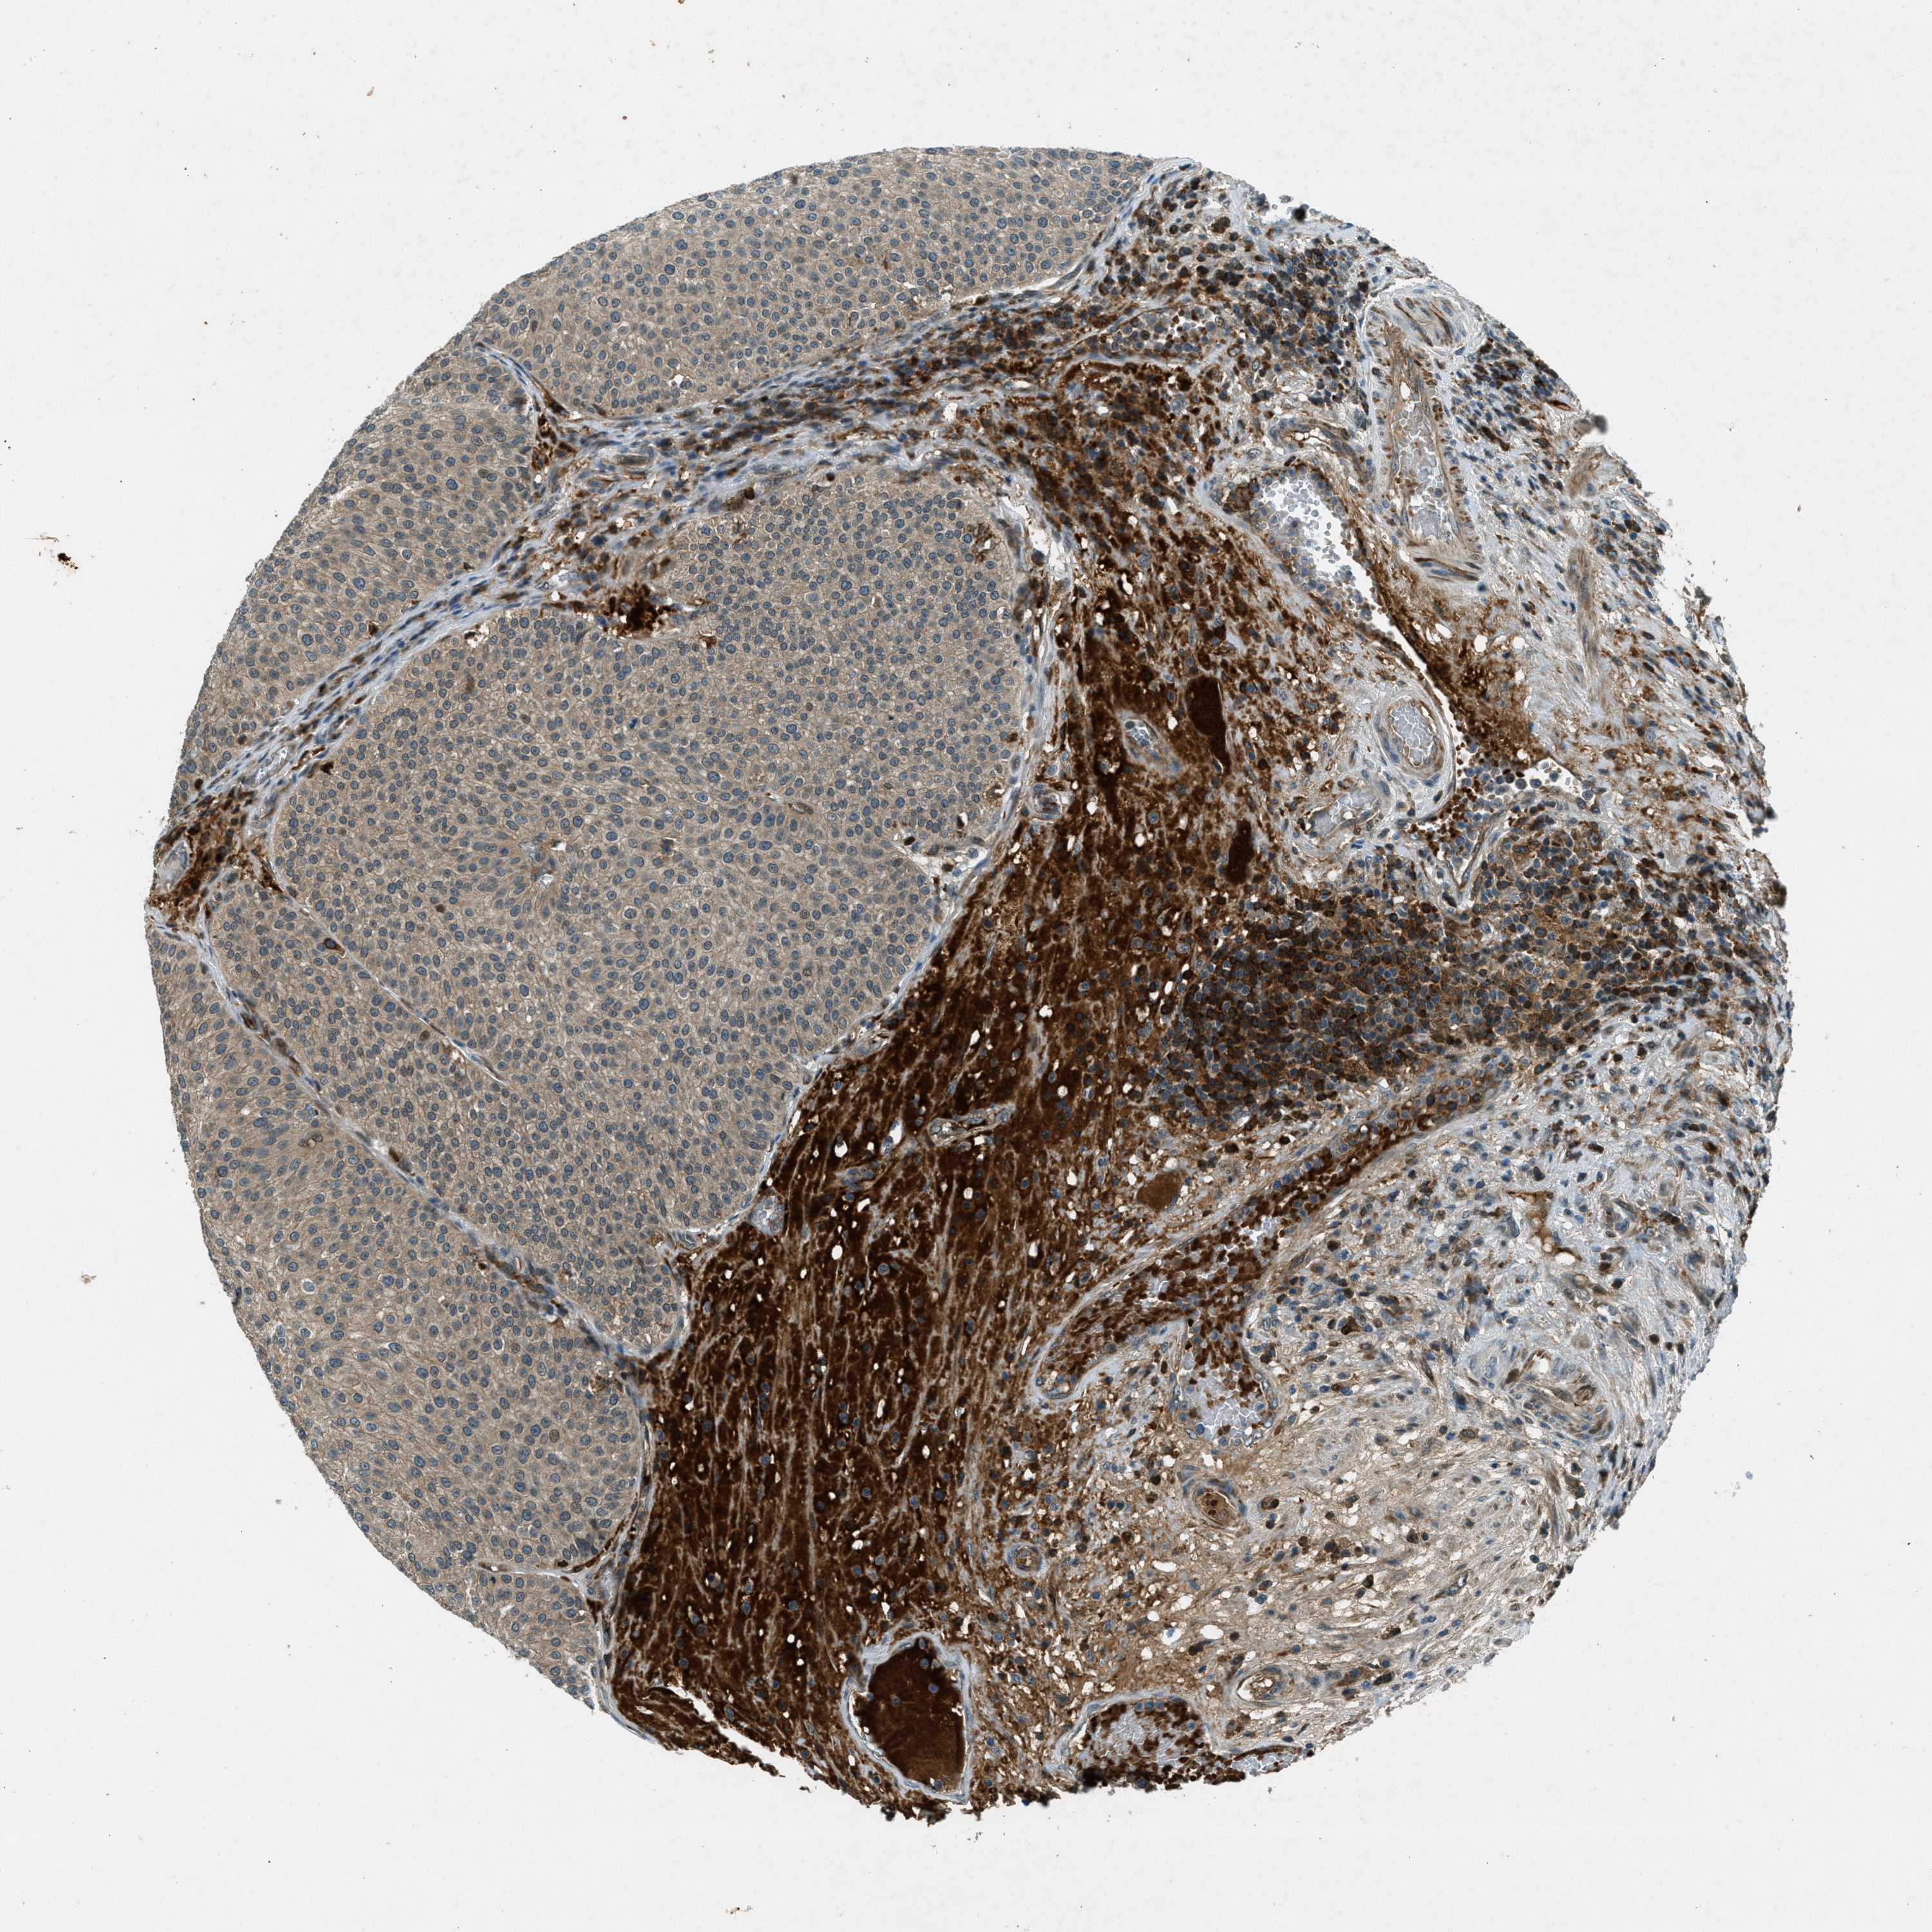

UROTHELIAL CANCER - Protein expressioni

A mouse-over function shows sample information and annotation data. Click on an image to view it in a full screen mode. Samples can be filtered based on level of antibody staining by selecting one or several of the following categories: high, medium, low and not detected. The assay and annotation is described here.

Note that samples used for immunohistochemistry by the Human Protein Atlas do not correspond to samples in the TCGA dataset.

Antibody stainingi

Antibody staining in the annotated cell types in the current human tissue is reported as not detected, low, medium, or high, based on conventional immunohistochemistry profiling in selected tissues. This score is based on the combination of the staining intensity and fraction of stained cells.

Each image is clickable and will lead to virtual microscopy that enables deeper exploration of all samples and also displays staining intensity scores, fraction scores and subcellular localization as well as patient and tissue information for each sample.

Antibody HPA017254

Antibody CAB016231

Antibody CAB022105

Staining

High

Medium

Low

Not detected

Intensity

Strong

Moderate

Weak

Negative

Quantity

>75%

75%-25%

<25%

None

Location

Nuclear

Cytoplasmic/membranous

Cytoplasmic/membranous,nuclear

Urothelial carcinoma, Low grade

Urothelial carcinoma, High grade